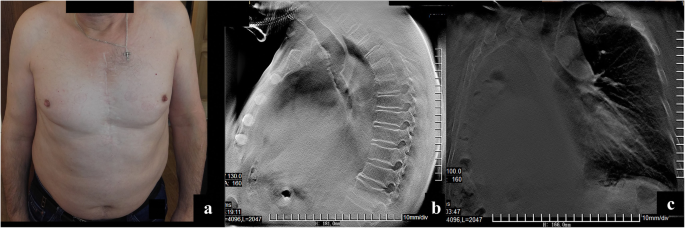

With subsequent follow-up, there was no TB relapse. In 2014 (5.5 years post-surgery), cancer recurrence in the upper third of the trachea along the anastomosis line was diagnosed. Radiation therapy was performed using a Theratron, resulting in complete tumor regression.

In April 2018, a central cancer of a three-segment bronchus on the left was revealed (an invasive highly differentiated squamous non-keratinized carcinoma). Radiation therapy and a course of chemotherapy (20 mg of nambin) were carried out with almost complete tumor regression. In July 2018 (10 years after the surgery), the patient’s condition is satisfactory and he reported no similar symptoms. (Fig. 3a-c, Fig. 4a-h).